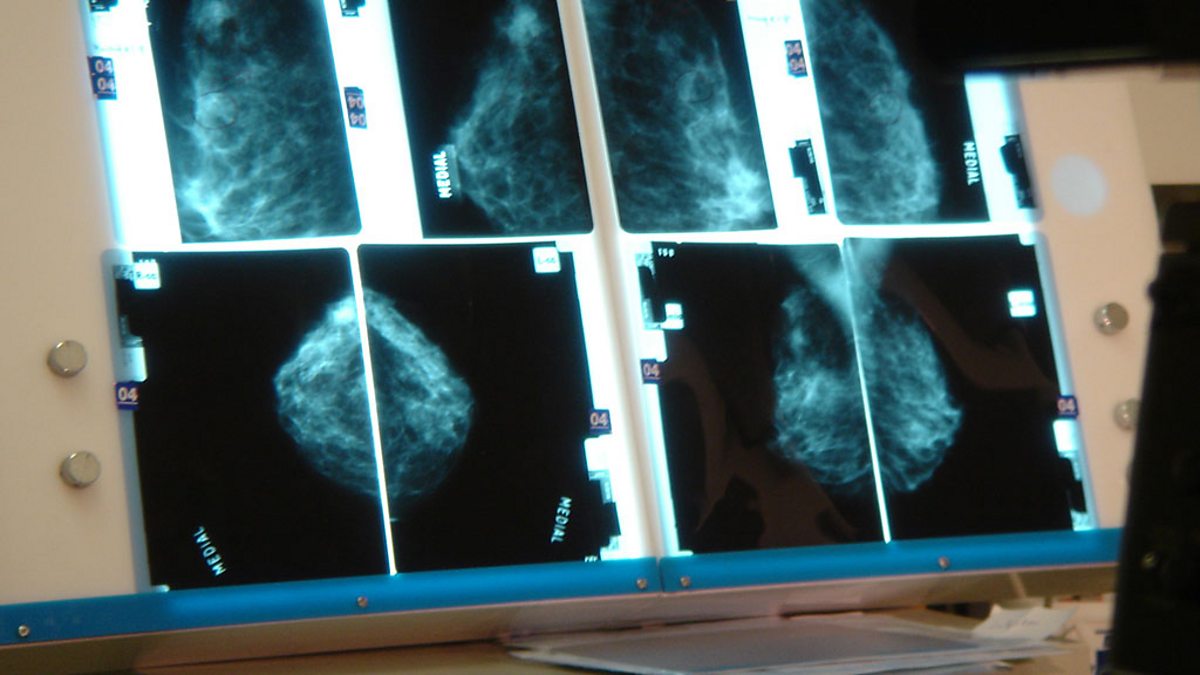

'We could prevent up to 30 per cent of breast cancer'

Prof Beral believes breast cancer could be cut significantly with a "hormonal vaccine".